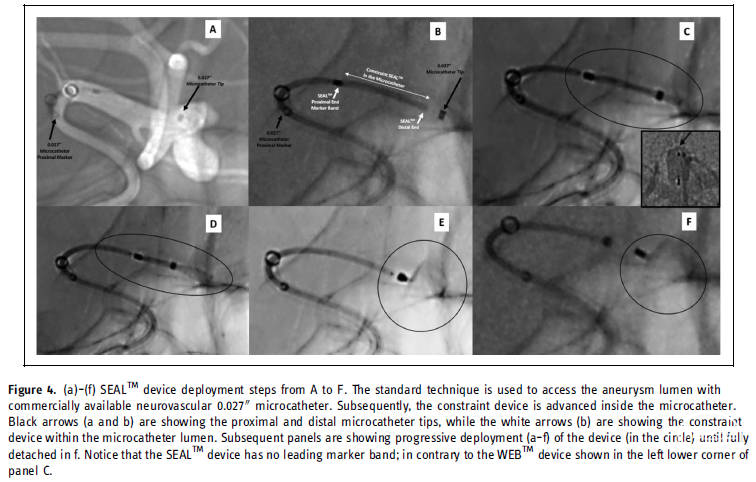

图4. SEAL™装置释放步骤。

SEAL™设备部署步骤。在选择SEAL™设备配置和尺寸后,Headway27微导管通过0.14微导丝置入动脉瘤腔内(图4b)。然后将SEAL™装置通过0.027内径的微导管推进,并通过推入和脱鞘方式毫无困难地部署到动脉瘤腔内(图4)。SEAL™设备有一个非创伤的、没有铅标记的远端头端,在透视下清晰可见近端标志物,如图4b-f(白色箭头和圆)。该装置使用电解脱控制器来部署和完成分离。当SEAL™装置分离时,标记带不再与微导管尖端对齐(图4f)